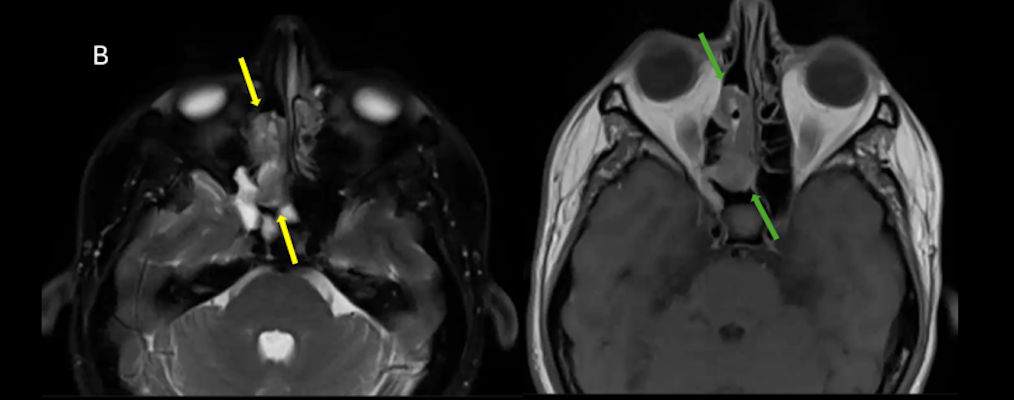

- B) Aksiyel T2A (oklar) ve T1A (oklar) görüntülerde lezyonun süperior nazal kavitede ve ara sinyal intensitede olduğu izleniyor.

- Estezionöroblastom görüntülemede tipik olarak nazal kavite tavanında, lamina cribrosa düzeyinden köken alan, etmoid sinüsler, orbita ve anterior kraniyal fossaya yayılım gösterebilen lobüle, agresif karakterli bir yumuşak doku kitlesi olarak izlenir ve sıklıkla komşu kemik yapılarda destrüksiyona neden olur. MR’da lezyon genellikle T1-ağırlıklı serilerde izo/hipointens, T2-ağırlıklı serilerde hiperintens sinyal özelliği gösterir ve kontrast sonrası heterojen güçlü kontrastlanma izlenir. İntrakraniyal uzanım varlığında tümör ile frontal lob parankimi arasında izlenen peritümöral periferik kistik değişiklikler, estezionöroblastom için literatürde tanımlanmış ayırt edici ve spesifik bir MR bulgusudur.